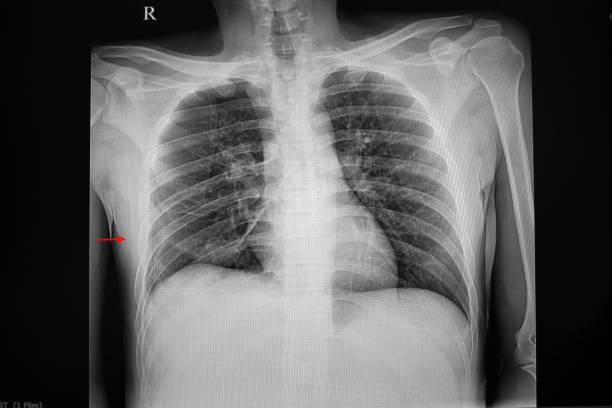

흉부 X선 검사

기흉이 의심되는 환자에게는 흉부 X선 검사를 실시하여 기흉이 있는지 확인할 수 있습니다. 이 방법은 비교적 쉽고 빠르게 기흉을 진단할 수 있습니다.